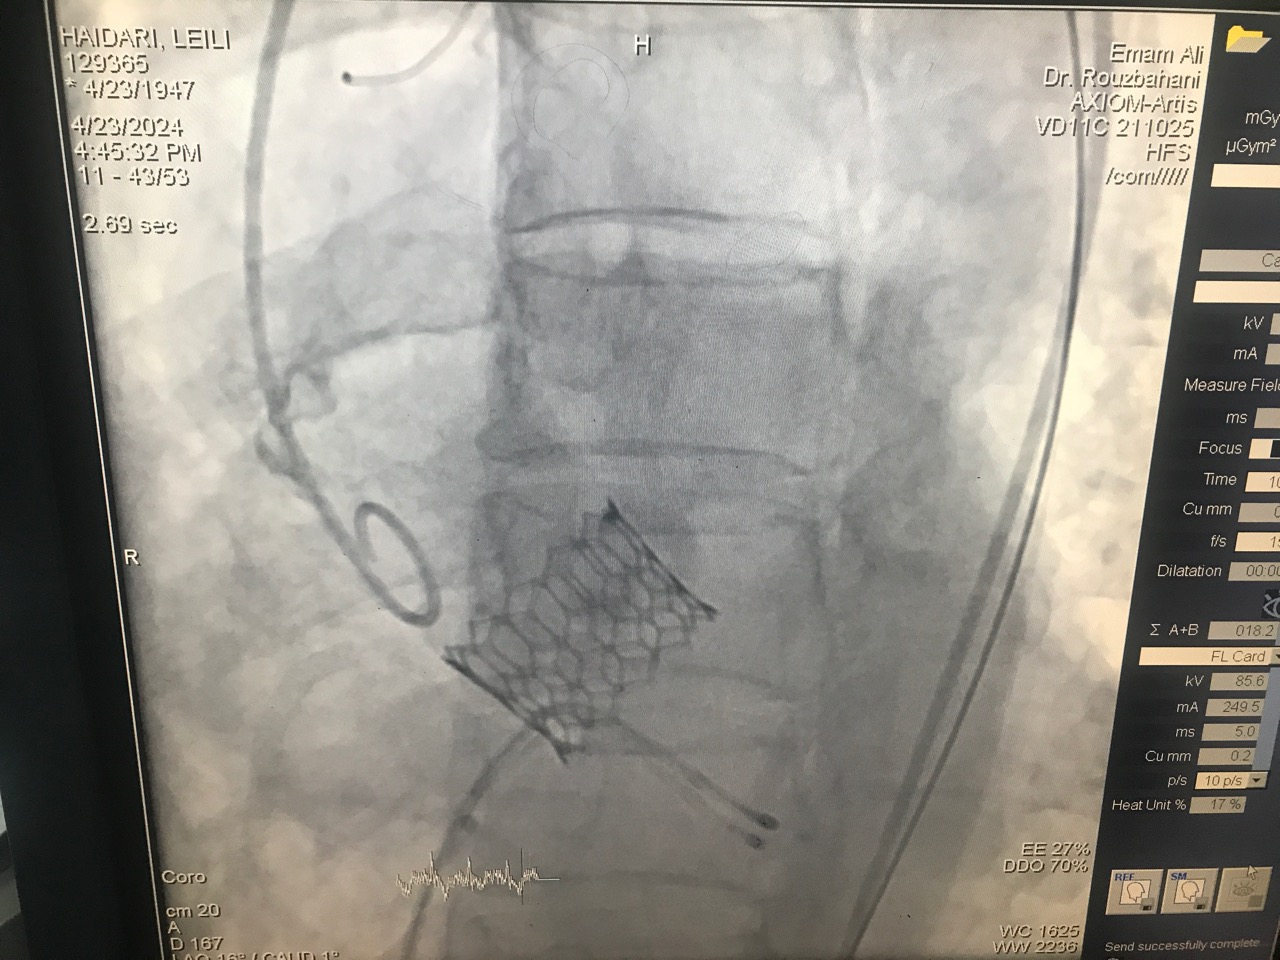

روز سه شنبه (۴ اردیبهشت ماه) عمل تاوی (تعویض دریچه قلب از طریق آنژیوگرافی) در بخش آنژیوگرافی قلب بیمارستان امام علی(ع) کرمانشاه  برای اولین بار در غرب کشور انجام شد.

در ادامه دکتر محمد روزبهانی فلوشیپ فوق تخصص آنژیوپلاستی و‌آنژیوگرافی و‌ مدیر گروه قلب و عضو هیأت علمی دانشگاه علوم‌پزشکی کرمانشاه نیز در خصوص عمل تاوی انجام گرفته در بخش آنژیوگرافی قلب بیمارستان امام علی(ع) کرمانشاه نیز اظهار کرد:  در این عمل متخصصان با وارد کردن کتتر یا همان فنر، از راه شریان فمورال (ران) وارد شریان آئورت قلب شده و دریچه جدید را در محل مناسب قرار می دهند که این مسئله باعث می‌شود فرایند ریکاوری و بهبود بیمار هم سریع‌تر اتفاق بیفتد.

به گفته دکتر روزبهانی ، پیش از این برای تعویض دریچه آئورت، جراحان به روش جراحی قلب باز به دریچه آئورت دسترسی پیدا می کردند و دریچه معیوب تعویض می شد اما از طریق این روش، دریچه با دقت بیشتر در جای مناسب تعبیه خواهد شد و اکنون این نخستین بار است که در بیمارستان امام‌ علی (ع) و در غرب کشور انجام می شود.